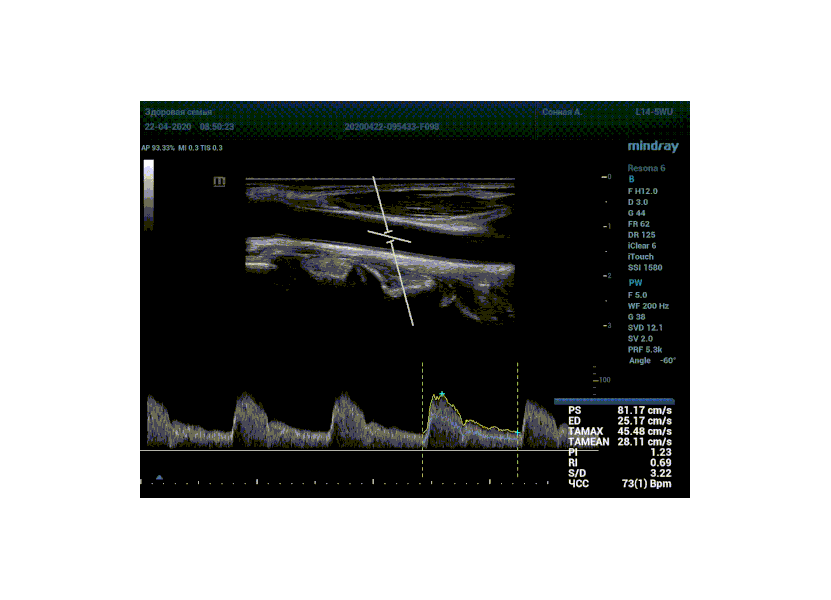

Алгоритм проводит измерения в режиме реального времени, выдавая результаты прямо на ходу. Не отвлекаясь на переключение режимов, остановку сканирования для измерений, а также ручной планиметрии спектра, достаточно просто нажать кнопку в калькуляторе с названием нужной артерии. Все значения сразу же попадут в отчет прибора, готовый к печати.

Особо ценна данная функция при исследовании тяжести стеноза. Доктор проводит санирование методом «утюжка» или же проводит «прогулку по стенозу» смещая зону опроса импульсно-волнового допплера. Таким образом проводит поиск максимальную скорость в струе элайзинга. Ранее максимальная скорость определялась на глазок, с дальнейшим измерением, либо серией измерений вручную. Теперь прибор сделает всё сам, без отрыва от движения, автоматически измеряя её в режиме реального времени.

Какие показатели выдает автоматический расчет? Доктор может настроить расчет под себя, под свои собственные желания. Стандартно выставлены показатели пиковой (PS) и конечной диастолической скорости (ED), TAMAX, TAMEAN, Pi, Ri, S/D соотношение и ЧСС. Можно дополнить из списка показателей: MD, PPG, Объемный поток, DT, AT, MPG, MMPG, VTI, D/S соотношение. Прибор подстраивается под Вас, а не вы под прибор.